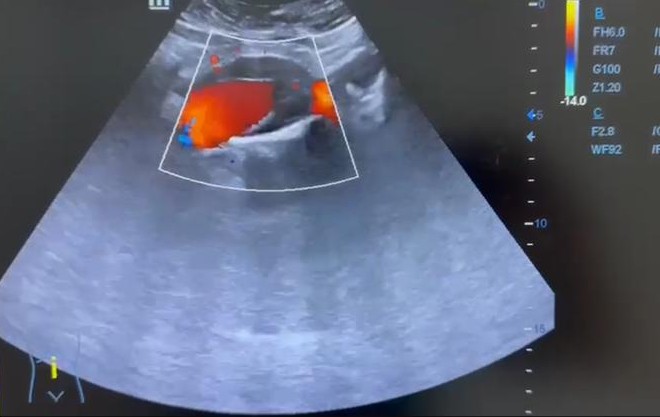

Ecografía clínica AP con los hallazgos siguientes: Presenta dilatación aneurismática de aorta infrarrenal fusiforme con trombo en su interior que disminuye la luz aórtica con diámetro 37,7 x 40,1 mm. Ambos riñones con forma y tamaño normales, buena diferenciación córtico medular sin signos de uropatía obstructiva.

Ante la clínica y los hallazgos ecográficos descritos, se derivó a urgencias hospitalarias para descartar disección aórtica. Realizan TC de abdomen con contraste informado de: Aneurisma de aorta infrarrenal con diámetro máximo de 48 mm de eje craneocaudal sin signos de ruptura inminente. La AMI sale del saco aneurismático. Extensión hasta porción proximal de ambas ilíacas. Aneurisma de arteria ilíaca común derecha de 17 x 15 mm. Dilatación de arteria ilíaca común izquierda de 10 x 11 mm.